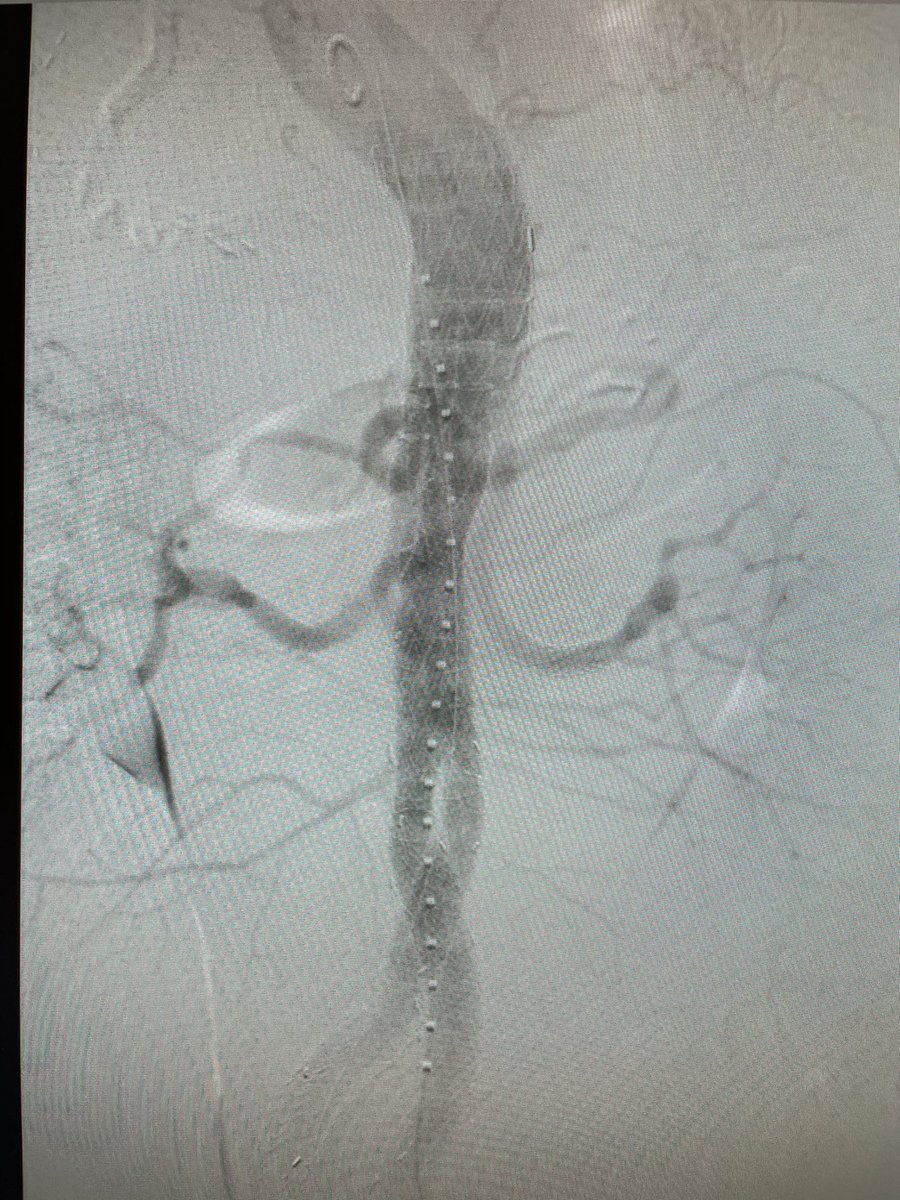

Congrats bjoernsuckow and team Dartmouth Hitchcock Vascular Surgery for another successful TAMBE case! Cutting edge aortic therapy Dartmouth-Hitchcock Heart and Vascular Center DartmouthSurgery Dartmouth Health | Inactive